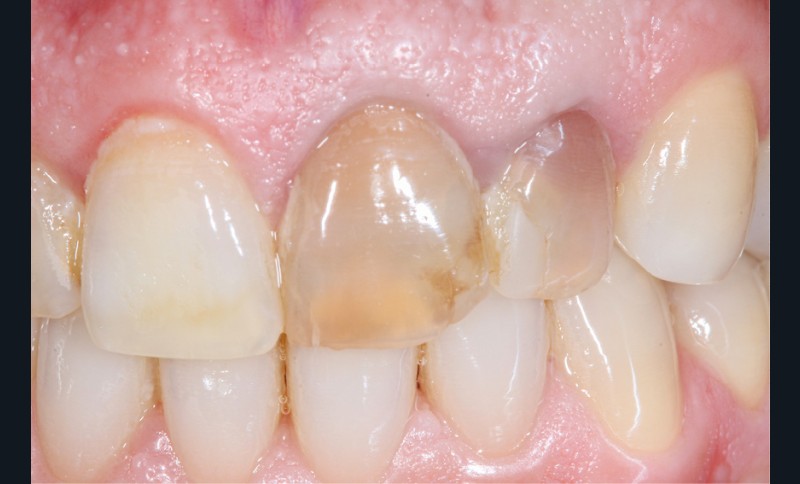

– Iatrogène (à la suite de traitements endodontiques ou à l’amalgame d’argent) (fig. 6a, b).